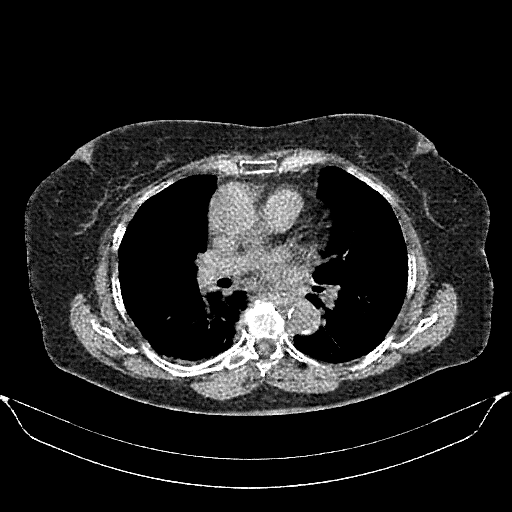

Image Grid

4Γ—3 grid: Rows show different image types (Original NATIVE, Reconstructed NATIVE, Original VENOUS, Generated VENOUS), Columns show windowing techniques (No Window, Lung Window, Mediastinum Window)

Original NATIVE CT scan (input)

No window - Raw intensity values

Reconstructed NATIVE CT scan (cycle consistency)

Original VENOUS CT scan

Generated VENOUS CT scan (A→B translation)